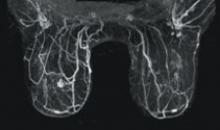

Magnetic resonance has long been used as a tool for spotting tumors, but rarely viewed as a first line of defense in treating breast cancer. X-ray mammography is the gold standard, with MRI and other alternative imaging modalities coming into play when screens and biopsies prove inconclusive.